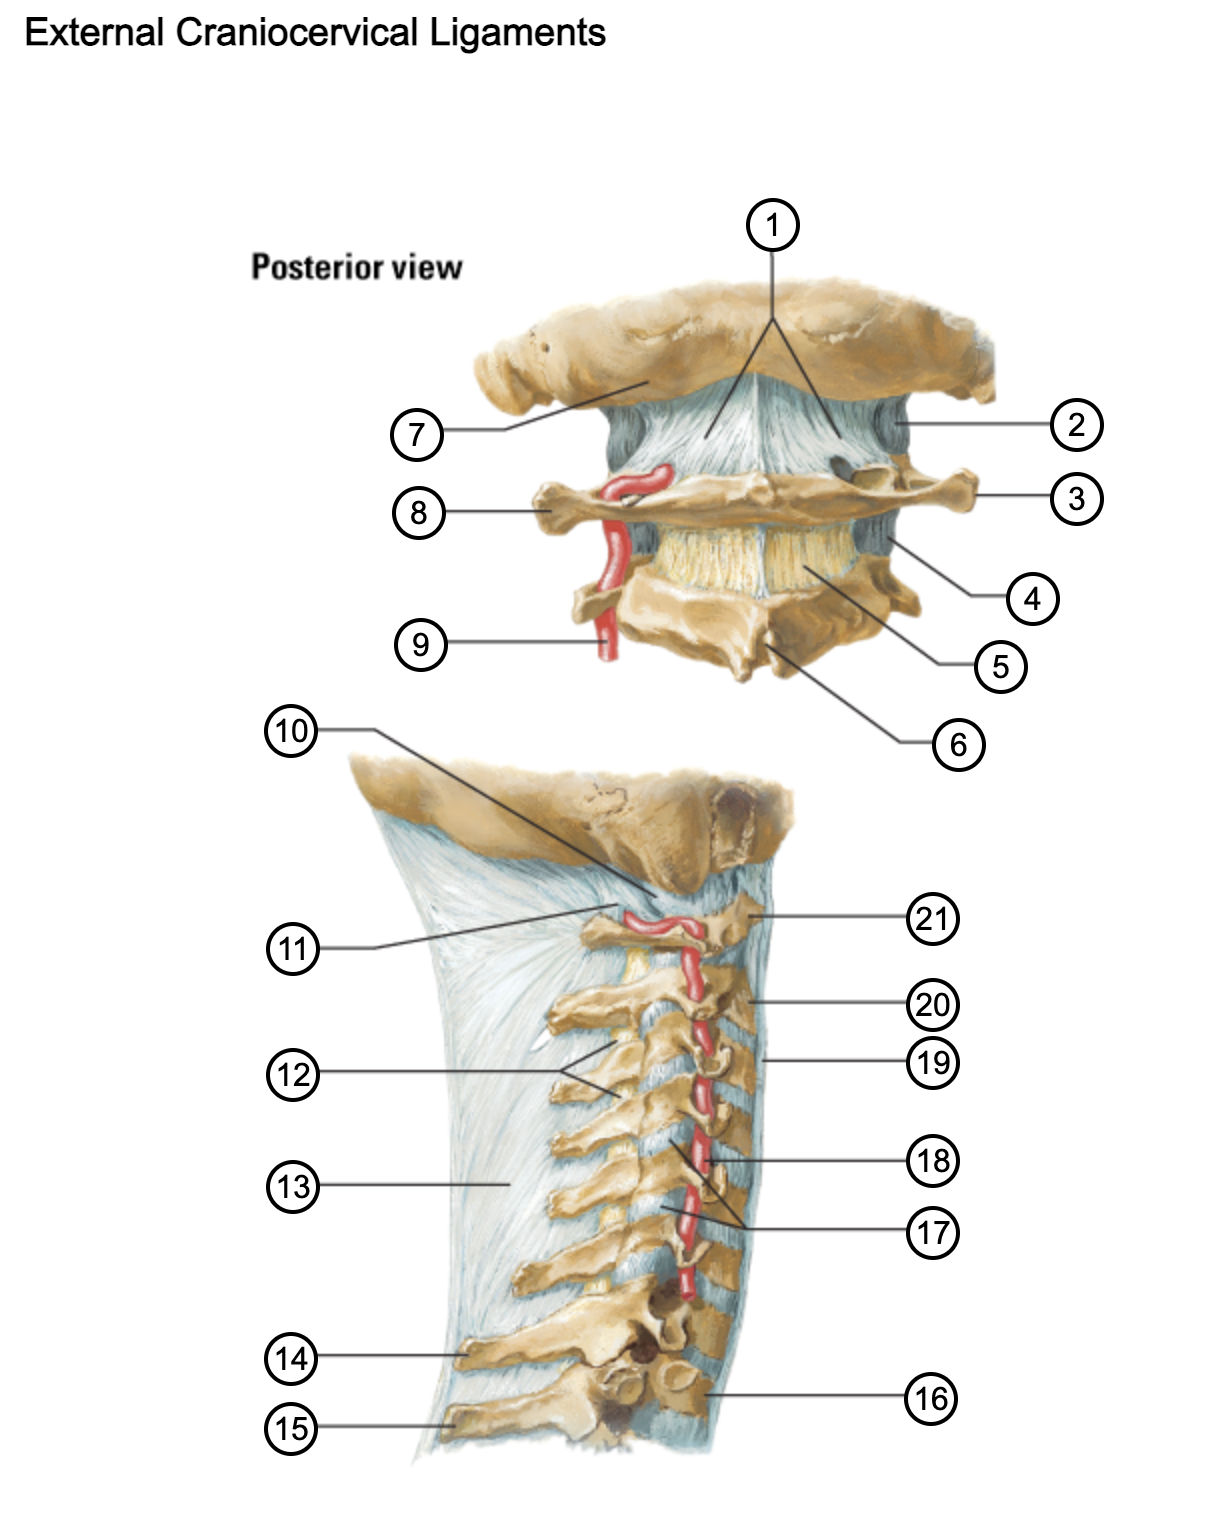

1

posterior antlantooccipital membrane

2

capsule of atlantooccipital joint

3

transverse process of atlas (C1)

4

capsule of lateral atlantoaxial joint

5

ligamenta flava

6

spinous process

7

occipital bone

8

transverse process of atlas (C1)

9

vertebral artery

10

capsule of atlantooccipital membrane

11

posterior atlantooccipital membrane

12

ligamenta flava

13

nuchal ligament

14

spinous process of C7 vertebra

15

spinous process of T1 vertebra

16

T1 vertebra

17

zygapophysical joints (C4-5 and C5-6)

18

vertebral artery

19

anterior longitudinal ligament

20

body of axis

21

Atlas (C1)